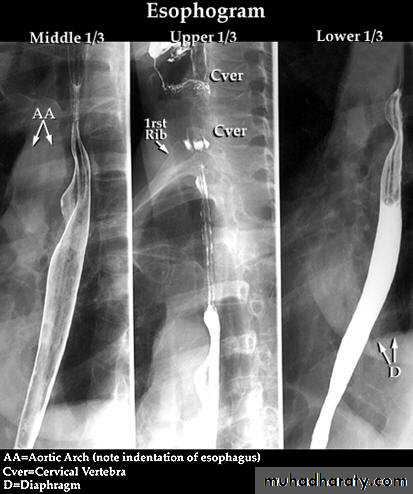

• THE OESOPHAGUSBarium Swallow:1. Conventional2. Double contrast (DC)3. Flouroscopy + spot films

Technique

1.Patient will need to be NPO after midnight before the exam2.The patient will have to swallow a contrast agent: Barium or Gastrografin

May also swallow sodium bicarbonate for double contrast barium swallow

3.X-ray tech will have the patient perform various maneuvers so that the barium can coat the GI tract

Esophagus mucosa: normal thin, parallel, uniform mucosal folds 3-4 in no.in double contrast examination